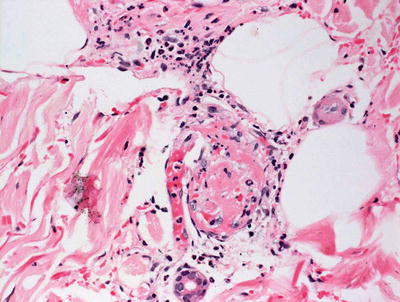

Fig. 11.2

Necrotic epidermis is seen overlying papillary dermal edema and a mild perivascular lymphocytic infiltrate in toxic shock syndrome